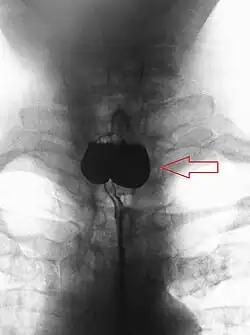

En anatomie, un diverticule de Zenker est un diverticule (une poche) de pulsion qui se forme au-dessus du sphincter œsophagien supérieur entre le faisceau thyroïdien du muscle constricteur inférieur et le faisceau cricoïdien du muscle constricteur inférieur (aussi appelé muscle cricopharyngien).

Le diagnostic est radiologique. Aujourd'hui l'imagerie de première intention à effectuer est un scanner cervico-thoraco-abdomino-pelvien avec opacification digestive haute ainsi qu'injection de produit de contraste. Le transit œso-gastro-duodénal historiquement utilisé qui visualise le diverticule sous forme d'une image d'addition du tiers supérieur de l'œsophage n'a pratiquement plus d'indication à l'heure actuelle en raison de la meilleure précision de l'examen TDM[1].